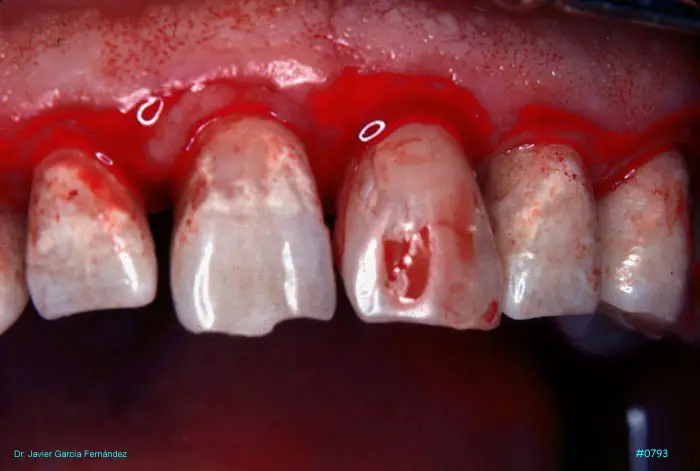

Atlas of Surgical Techniques in Periodontics. Chapter III. Atlas de Técnicas Quirúrgicas en Periodoncia